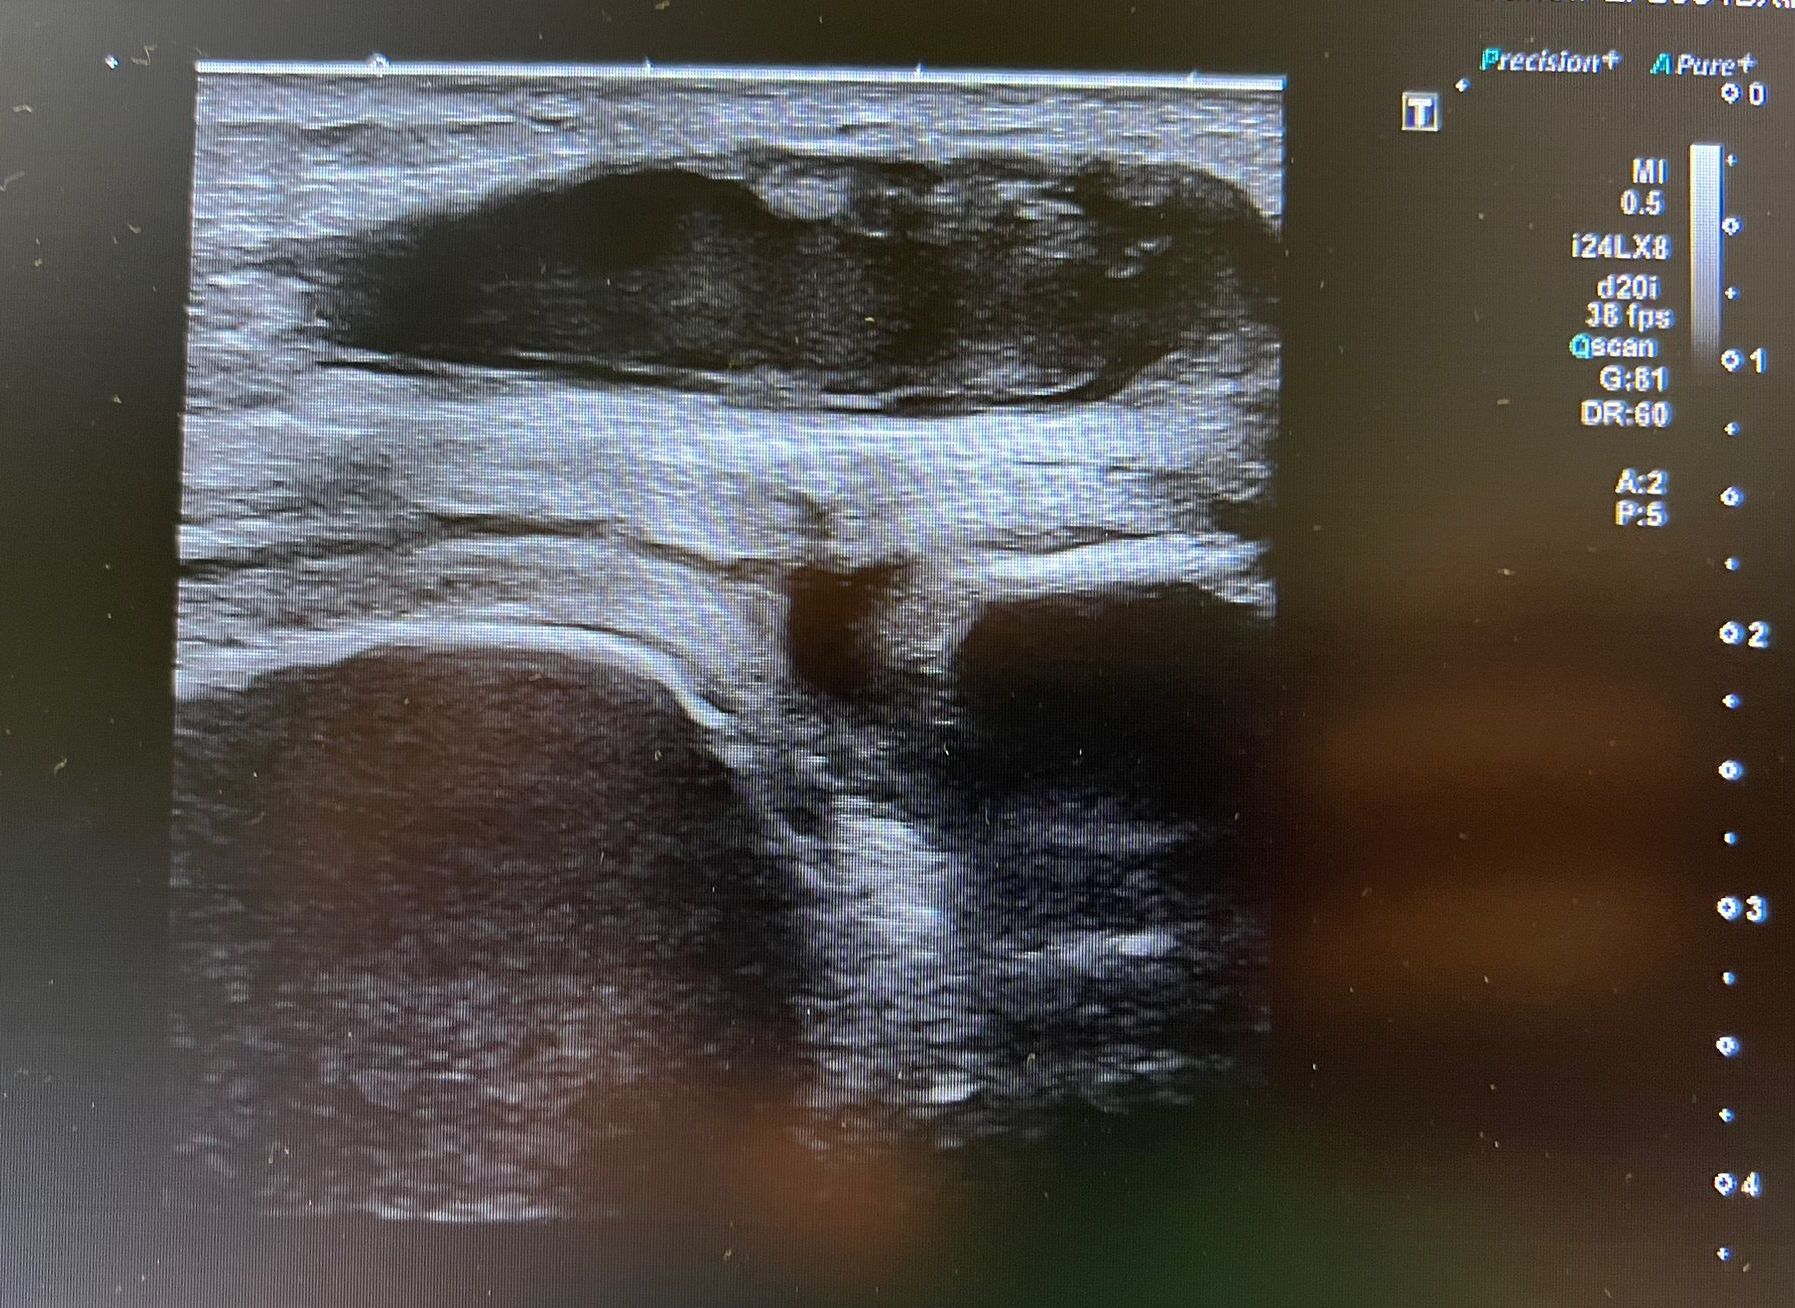

Hallazgos ecográficos

Se realiza ecografía clínica en la que se aprecia colección heterogénea en bursa prerrotuliana así como edema de partes blandas. No aumento de líquido ni colecciones a nivel intraarticular sugestivas de artritis séptica.